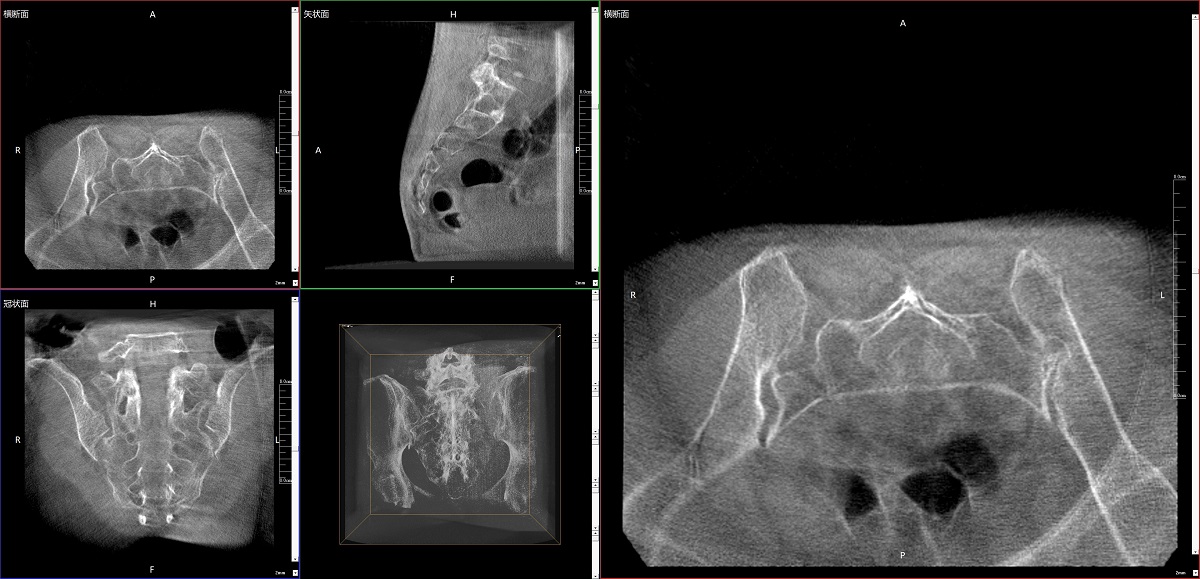

在骨科手術(shù)中,影像相當于醫(yī)生的“眼睛”,要先“看得清",才能“算得準” “打得穩(wěn)”。普愛醫(yī)療第三代平板三維C形臂協(xié)同醫(yī)院創(chuàng)傷導航機器人已開展多例“骨盆骨折微創(chuàng)手術(shù)”,成為上海市第七人民醫(yī)院手術(shù)技術(shù)創(chuàng)新的一大亮點。

普愛醫(yī)療第三代平板三維C形臂出色的二維透視和術(shù)中三維成像效果,為機器人提供了精確的術(shù)中影像依據(jù),協(xié)同提升手術(shù)整體的精準度和效率,為患者帶來了更安全、更高效的醫(yī)療服務體驗。